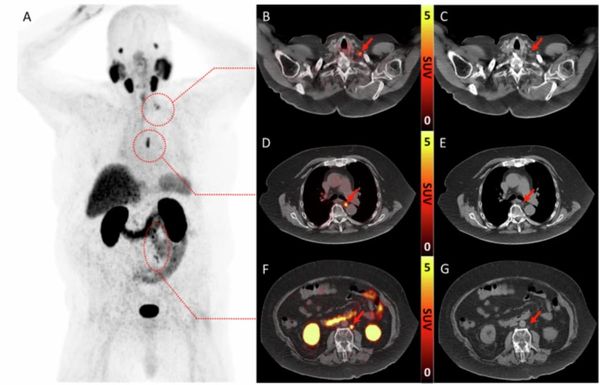

In a prospective study comparing PSMA PET/CT and mpMRI for biopsy- and imaging-naïve men with suspected prostate cancer (PCa), PSMA PET/CT led to altered management in 34 percent of confirmed cases of PCa.